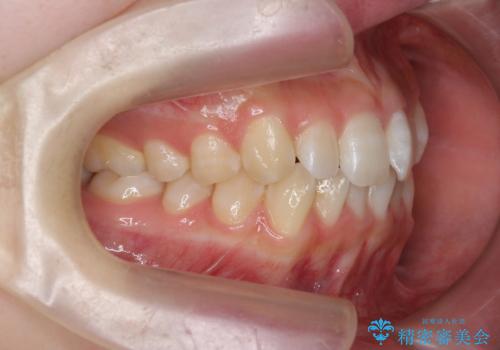

前歯のねじれを治したい マウスピース矯正治療

- 前歯のねじれを改善し、きれいな歯並びにしたい!と矯正治療を希望され来院されました。

マウスピース矯正システム、インビザラインのシミュレーションを用いて最終的な歯の位置をしっかりと確認したのち、きれいな歯並びとなるようマウスピース矯正治療を開始します。

ねじれとともに突き出たように見えていた前歯も見た目が大きく改善し、喜んでいただくことができました。